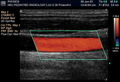

Eco Doppler.jpg 400 × 273; 69 KB